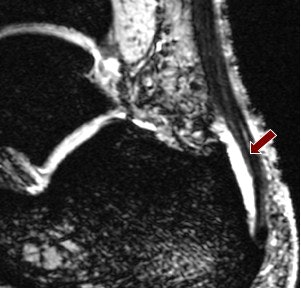

Fluid collection around tendons was apparent in all six runners at both field strengths, though visibility of this was clearer at 7-tesla using a multiple-echo data image combination (MEDIC) sequence, which produced a high contrast with the surrounding tissue.

| Above, 1.5-tesla image of bursal fluid in the ankle. Below, 7-tesla image shows superior depiction of the bursal fluid. Images courtesy of Dr. Patrick Kokulinsky. |